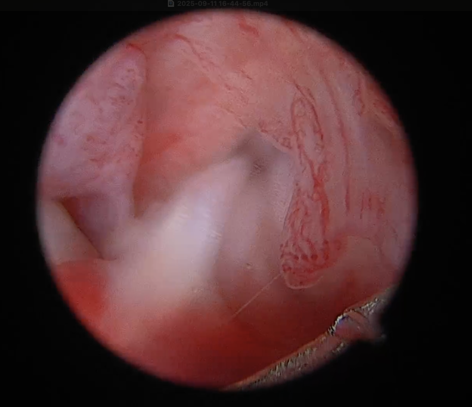

.png)

후방 십자인대 부분 손상 및 염증성 변화 확인

손상되지 않은 반월판 확인 된 모습